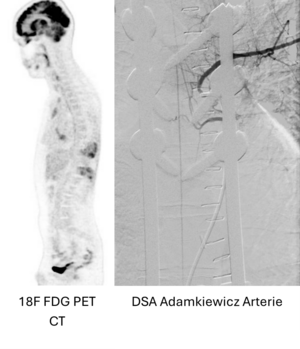

- Schmerzstillende stabilisierende Maßnahmen und Versteifungsoperationen bei primärem sowie sekundären Wirbelsäulentumoren (Metastasen)

Seit 2017 führen wir unsere Stabilisierungs- und Versteifungsoperationen mit einem intraoperativen CT (s.o. AIRO©, Fa. Brainlab) durch. Diese intraoperative Computertomographie liefert direkt im Operationssaal während des Eingriffs hochauflösende Bilder von der Wirbelsäule. Zusammen mit einer Navigationssoftware wird ein dreidimensionaler Plan der entsprechenden Körperregion erzeugt. Mit Hilfe der Bildgebung können wir die notwendigen OP-Schritte plangerecht umsetzen und z.B. Implantate mit sehr hoher Präzision einsetzen. Gerade bei komplizierten Eingriffen an der Wirbelsäule hilft die neue OP-Technik, Patienten sicher und schonend zu therapieren. Die intraoperative Bildgebung, direkt im OP, erlaubt komplexe Operationen genauer und sicherer durchzuführen und dem Operateur noch während der Operation das Ergebnis zu überprüfen und bei Bedarf zu optimieren. Belastende Folgeoperationen sind so deutlich seltener und die Behandlungsqualität und Sicherheit für Patienten dadurch erheblich verbessert.